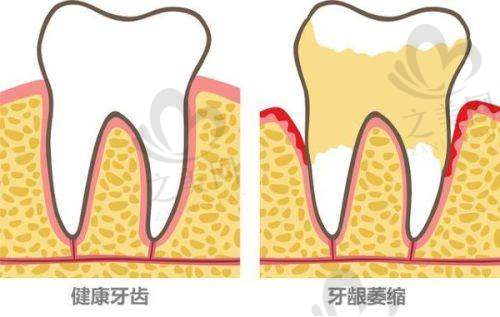

除了种植牙,医院还开展牙齿矫正、牙齿美容、牙周病治疗等多元化服务。它是时代天使、隐适美授权机构,矫正方案采用精良设计;拔牙、根管治疗可全程打“睡眠麻醉”,让患者在舒适的状态下完成治疗。